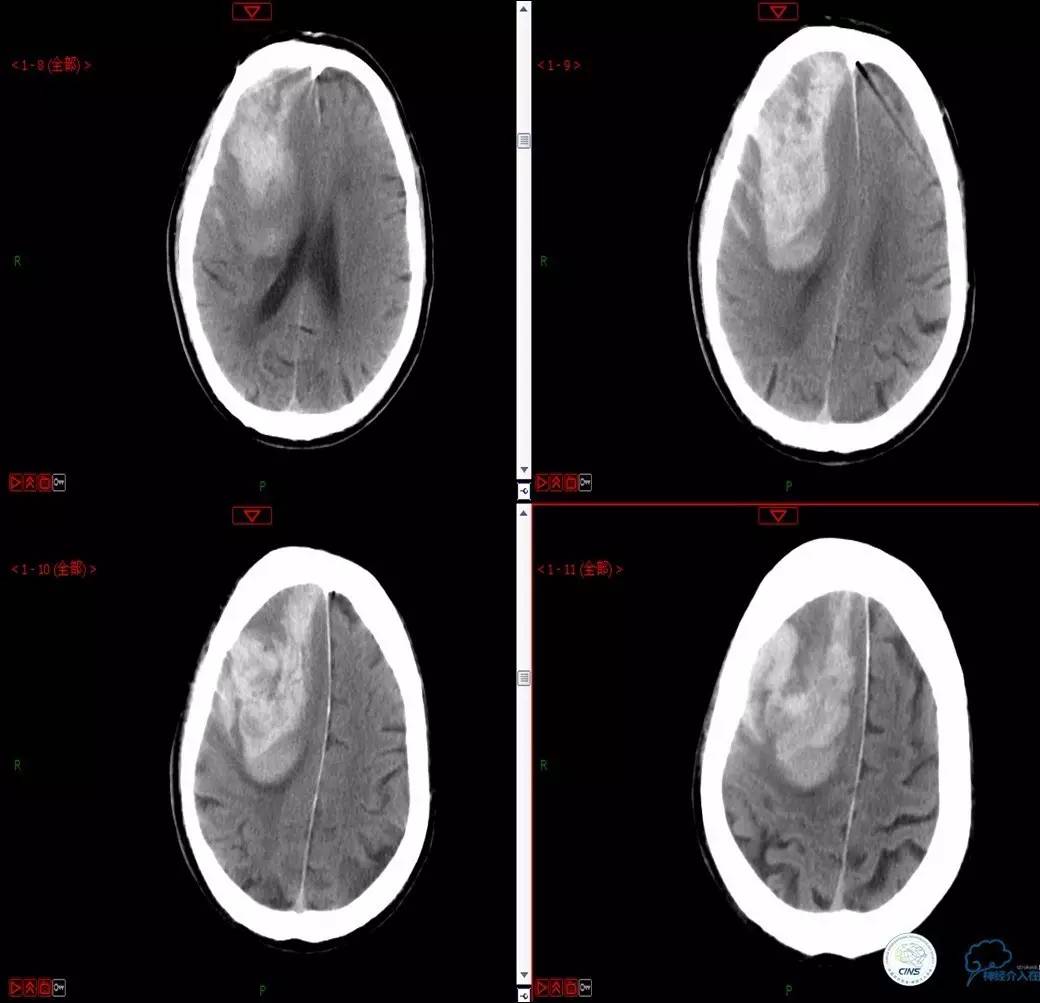

》男,74岁。

》主诉:突发左侧肢体抽搐伴口角歪斜两月余,右侧肢体抽搐三天余。

》查体:左上肢肌力Ⅲ级,左下肢肌力Ⅳ级,右侧肢体肌力Ⅴ级。

》既往史:高血压病史。

》患者术后4小时出现右侧肢体无力,伴有癫痫样症状。

》考虑小栓子脱落,术中曾有后扩。